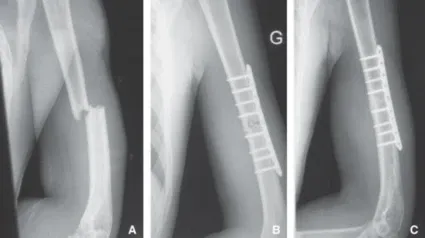

La fisura es una fractura pero sin desplazamiento del hueso